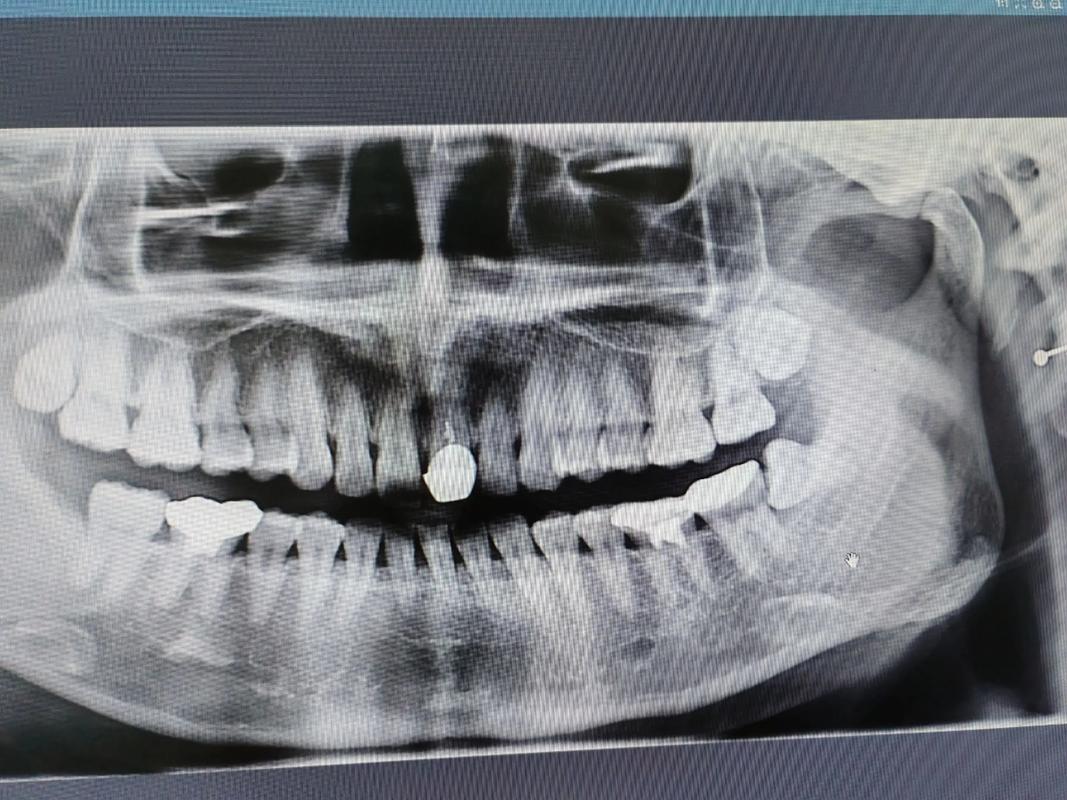

- 对于大多数常规的正畸病例(如简单的牙齿拥挤、前突、反颌等),仅靠传统的二维X光片(如全景片、头颅侧位片)和临床检查就足够了。

- 对于一些复杂的、涉及骨骼、埋伏牙、种植支抗或需要精确评估骨量的情况,口腔CT(CBCT)是极其重要甚至不可或缺的诊断工具。

- 埋伏牙定位: 对于未萌出的牙齿(如埋伏阻生智齿、尖牙、多生牙),CBCT能清晰显示牙齿在颌骨内的精确位置、萌出方向、牙根形态以及与邻牙、重要解剖结构(如下颌神经管)的关系,这是二维片无法比拟的,对制定手术导萌或正畸牵引方案至关重要。

- 牙根位置与吸收: 可以清晰观察牙根在牙槽骨内的位置、有无弯曲、以及是否有牙根吸收(尤其是正畸治疗过程中或治疗后需要评估时)。

- 埋伏牙(尤其是位置复杂、靠近神经管或邻牙根尖)的定位和诊断。

- 怀疑有严重的牙根吸收或需要评估牙根位置。

- 对于一些疑难杂症,二维影像无法明确诊断时。